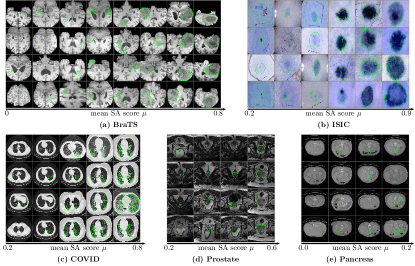

Refer to caption

Figure 12: The ranking list of images based on the mean SA score μ𝜇\mu on the five datasets. The segmentation maps of the images with a low mean SA score μ𝜇\mu need more attention.

Figure 13: Examples of the (a) input images (with ground-truth highlighted with green contours), the corresponding (b) heat-maps computed based on the segmentation of units on last two years and (c) outputs of neural network. The corresponding mean SA score and Dice score are shown on the bottom of each image.

Fig. 10 shows the relationship between the performance of the neural network and the mean SA score μ𝜇\mu of the units from the last two convolutional layers. The segmentation performance of the network correlates to the mean SA score μ𝜇\mu on all five datasets. For images with a high mean SA score μ𝜇\mu, the Dice score of the neural network’s output \mathcal{B} is also high. We also compare it with the Variance of Gradients (VoG) [1] which is used for ranking the test images. VoG is specifically designed for image classification. Fig.10 shows that the correlations between the VoG score and segmentation accuracy (Dice) are smaller than the correlations between the mean SA score μ𝜇\mu and segmentation accuracy for medical image segmentation on the five datasets. Fig. 12 shows the ranking list of images based on the mean SA score μ𝜇\mu. Images with a low mean SA score μ𝜇\mu is the difficult images which need more attention in practice. Thus, the mean SA score is a meaningful measurement for ranking the test images without ground-truth by difficulty and surfacing a tractable subset of the most difficult test images for human-in-the-loop auditing [1]. Fig. 13 shows examples of the image with heat-maps and outputs from the neural network. The corresponding mean SA scores of segmentation maps on deep features and Dice scores of the neural network’s output are also shown on each image. From the example images we can see that images with small objects or smooth boundaries usually have a low mean SA score μ𝜇\mu and the segmentation performance of the output is also low. Therefore, the performance of segmentation is mainly affected by the small objects or objects with the smooth boundaries which usually have a small mean SA score μ𝜇\mu. Put simply, smaller and blurry objects are more difficult to segment.